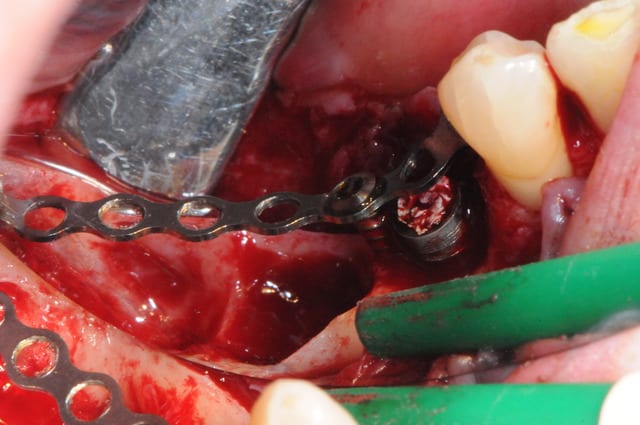

4 après un long moment de nettoyage, de curetage, de surfaçage implantaire, d'aeropolissage de l'implant, etc...

on fini enfin par arriver à ça.

ah oui, j'ai passé 2 fois un bon gros quart d'heure à gérer deux petites artères intra-osseuses de me..e qui m'ont vraiment pourri ma zénitude per-op.

de vraies petits geysers! ça doit faire dix ans que j'en avais pas eu des comme ça.

j'en viens maintenant au système FAST de Joseph.

1- les vis et la chaine titane adaptée aux vis.

(pour expliquer: ce système permet de maintenir la chaîne en l'air par sa tête.)

4-5-6-7 sciage de la mesh titane et positionnement in situ d'un bout à l'autre de l'arcade.